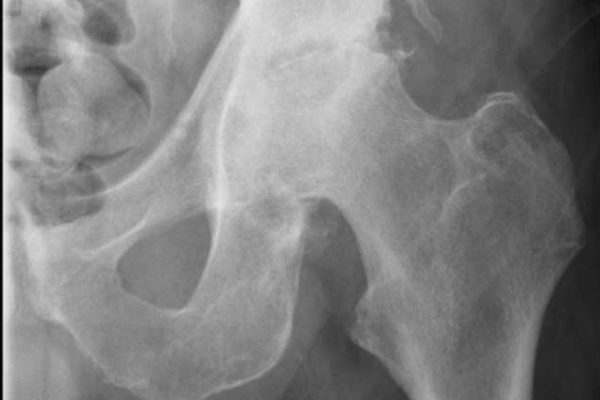

[/vc_column_text][/vc_column][/vc_row][vc_row type=”full_width_background” full_screen_row_position=”middle” column_margin=”default” column_direction=”default” column_direction_tablet=”default” column_direction_phone=”default” bg_color=”#f4f4f4″ scene_position=”center” top_padding=”70″ bottom_padding=”60″ text_color=”dark” text_align=”center” row_border_radius=”none” row_border_radius_applies=”bg” overflow=”visible” overlay_strength=”0.3″ gradient_direction=”left_to_right” shape_divider_position=”bottom” bg_image_animation=”none”][vc_column column_padding=”no-extra-padding” column_padding_tablet=”inherit” column_padding_phone=”inherit” column_padding_position=”all” column_element_direction_desktop=”default” column_element_spacing=”default” centered_text=”true” desktop_text_alignment=”default” tablet_text_alignment=”default” phone_text_alignment=”default” background_color_opacity=”1″ background_hover_color_opacity=”1″ column_backdrop_filter=”none” column_shadow=”none” column_border_radius=”none” column_link_target=”_self” column_position=”default” gradient_direction=”left_to_right” overlay_strength=”0.3″ width=”1/1″ tablet_width_inherit=”default” animation_type=”default” bg_image_animation=”none” border_type=”simple” column_border_width=”none” column_border_style=”solid”][vc_column_text]Arthritis refers to a group of conditions affecting the body’s joints, including the bone, muscle, and surrounding soft tissues. The most common symptoms are joint pain, stiffness, and reduced function, which can lead to disability and reduced quality of life.

Arthritis is a common condition affecting 3.5 million Australians, which is about 15 per cent of the population. Osteoarthritis (OA) and rheumatoid arthritis (RA) are the two most common types. Arthritis has no cure, but its symptoms can be successfully managed with exercise, weight loss, lifestyle changes, and appropriate medication. When symptoms become unmanageable, joint replacement surgery can be considered.